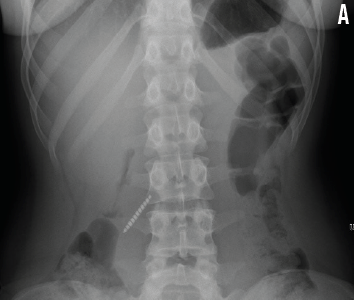

Ameer Hassoun, MD; Yagnaram Ravichandran, MD; Jonathan Rochlin, MD

A 15-year-old girl presented to the emergency department (ED) 1 hour after having swallowed her toothbrush.

08/27/2015